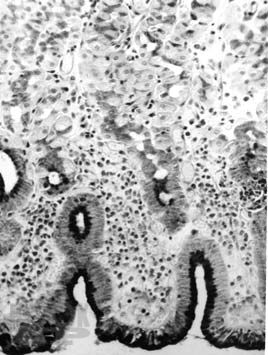

В небольшой по объему монографии представлена краткая анатомо-гистологическая характеристика нормальной слизистой оболочки желудка и двенадцатиперстной кишки, рассматривается морфологическая классификация гастритов и гастропатий, а также сущность дистрофических, воспалительных и дисрегенераторных изменений слизистой оболочки желудка при различных формах гастродуоденальной патологии. Приводятся краткие сведения об основных правилах гистологической техники, знание которых необходимо клиницисту. Основная цель пособия — дать молодому врачу представление об основах морфологической диагностики заболеваний желудка. Книга также может быть полезной для первичного образования и совершенствования гастроэнтерологов, клинических морфологов, эндоскопистов, а также для врачей других специальностей.